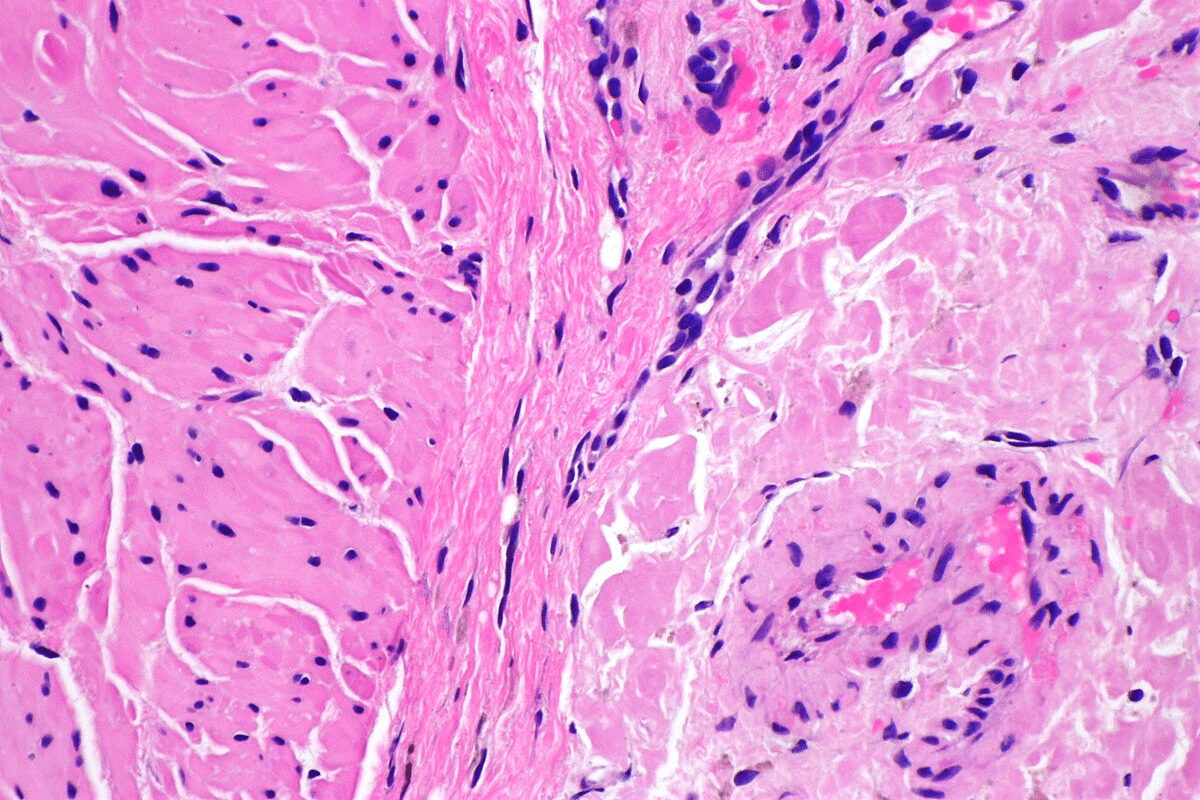

Testing and Biopsy Procedures

To figure out if you have amyloidosis, doctors use several tests. These include blood and urine tests, bone marrow biopsies, and imaging like echocardiograms or MRIs. A biopsy of the affected organ is usually needed to find amyloid deposits directly.

Biopsies are very important for diagnosing amyloidosis. Where to take the biopsy depends on the organs affected and your health. For example, a fat pad biopsy is sometimes used for systemic amyloidosis and is less invasive.